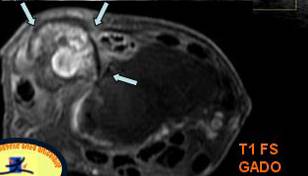

COMPRESIUNEA NERVULUI ULNAR PRIN OSTEOCONDROM SECUNDAR

Parestezii in teritoriul nervului ulnar Mica osificare →in contact cu n. Ulnar → Pe IRM mica lacuna osteocondrala a condilului →* corespunzator locului de plecare a osteocondromului